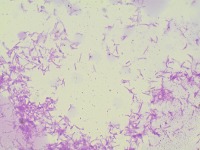

bacterial-image-classification Computer Vision Project

bacteriaclassification

Classes (78)

A description for this project has not been published yet.